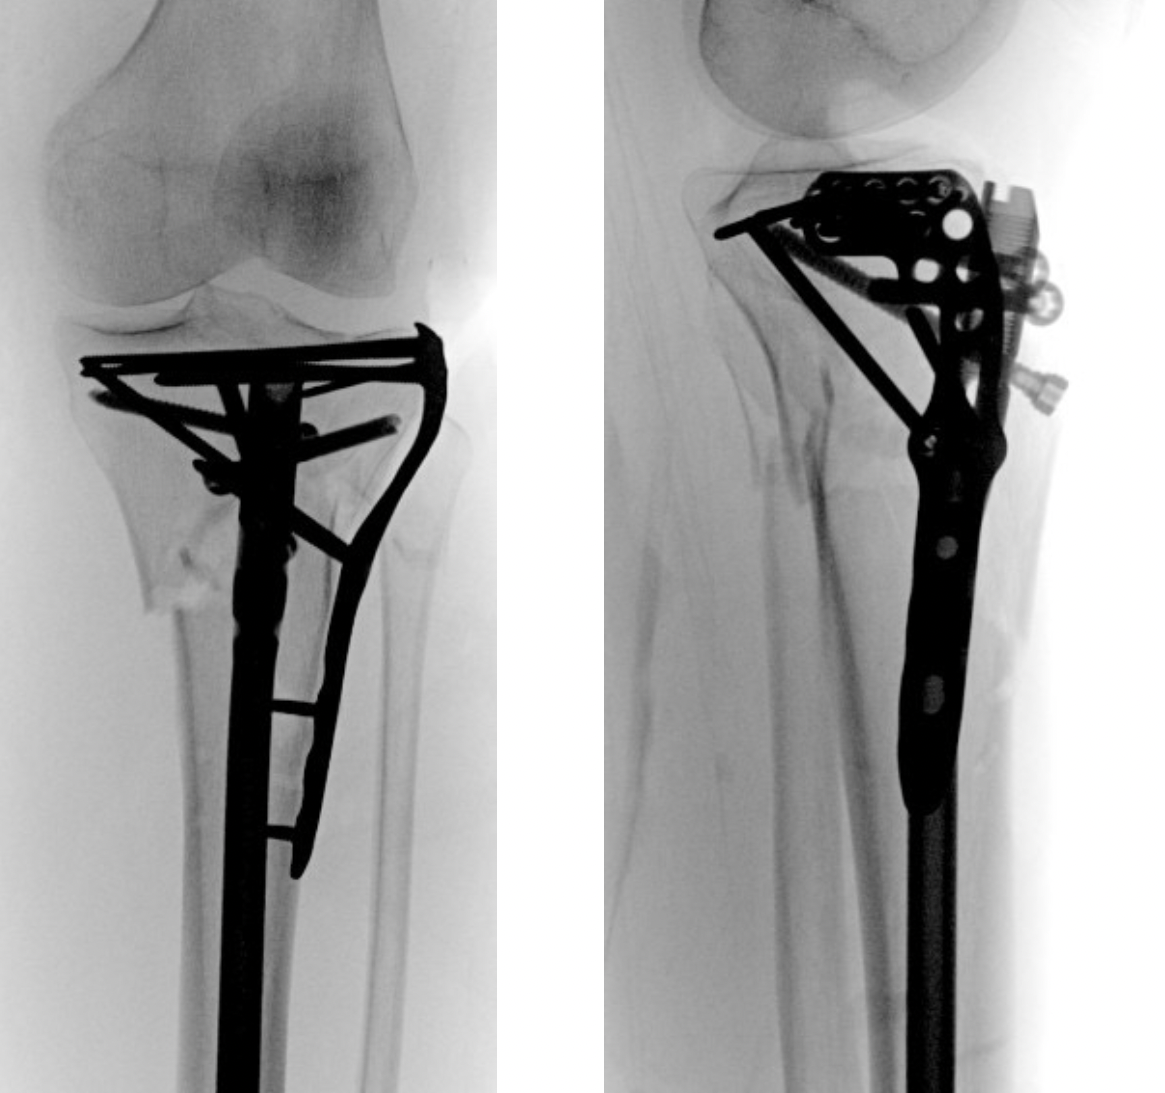

1. Change entry point

- match entry point to distal IM canal

- lateral in line with lateral tibial spine

- posterior

2. Blocking screws

- also lateral and posterior

- functionally narrow IM canal

- on concave side of deformity at the level of the fracture

- same positions as entry point

- posterior in proximal segment adjacent to fracture

- lateral in proximal segment adjacent to fracture

Smith and Nephew Tibial Meta Nail with Blocking Screws

3. Supra-patellar approach with leg semi-extended

- flexed tibia tends to accentuate the deformity

- semi-extended reduces the deformity

- also easier to get lateral and posterior entry point

Smith & Nephew Semi-extended nail

Vumedi Proximal Tibial Nailing Presentation